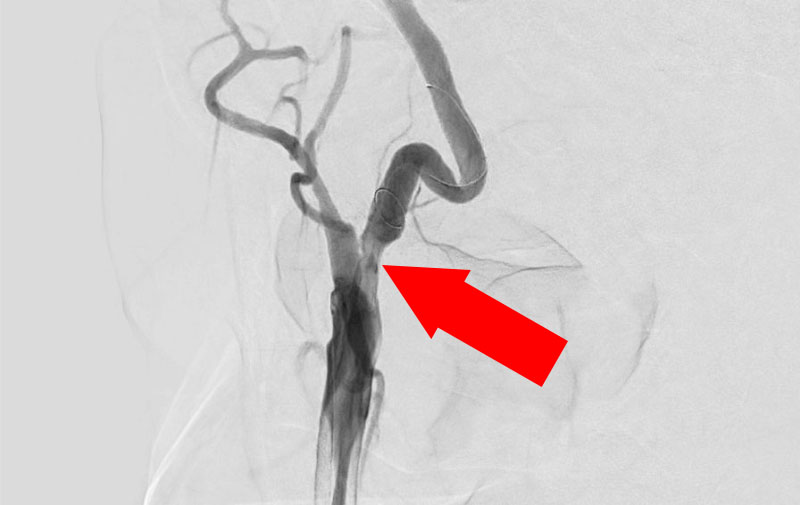

No.1328 手術前

No.1328 手術中

No.1328 手術後

左総頚動脈狭窄症

50代

院内外来